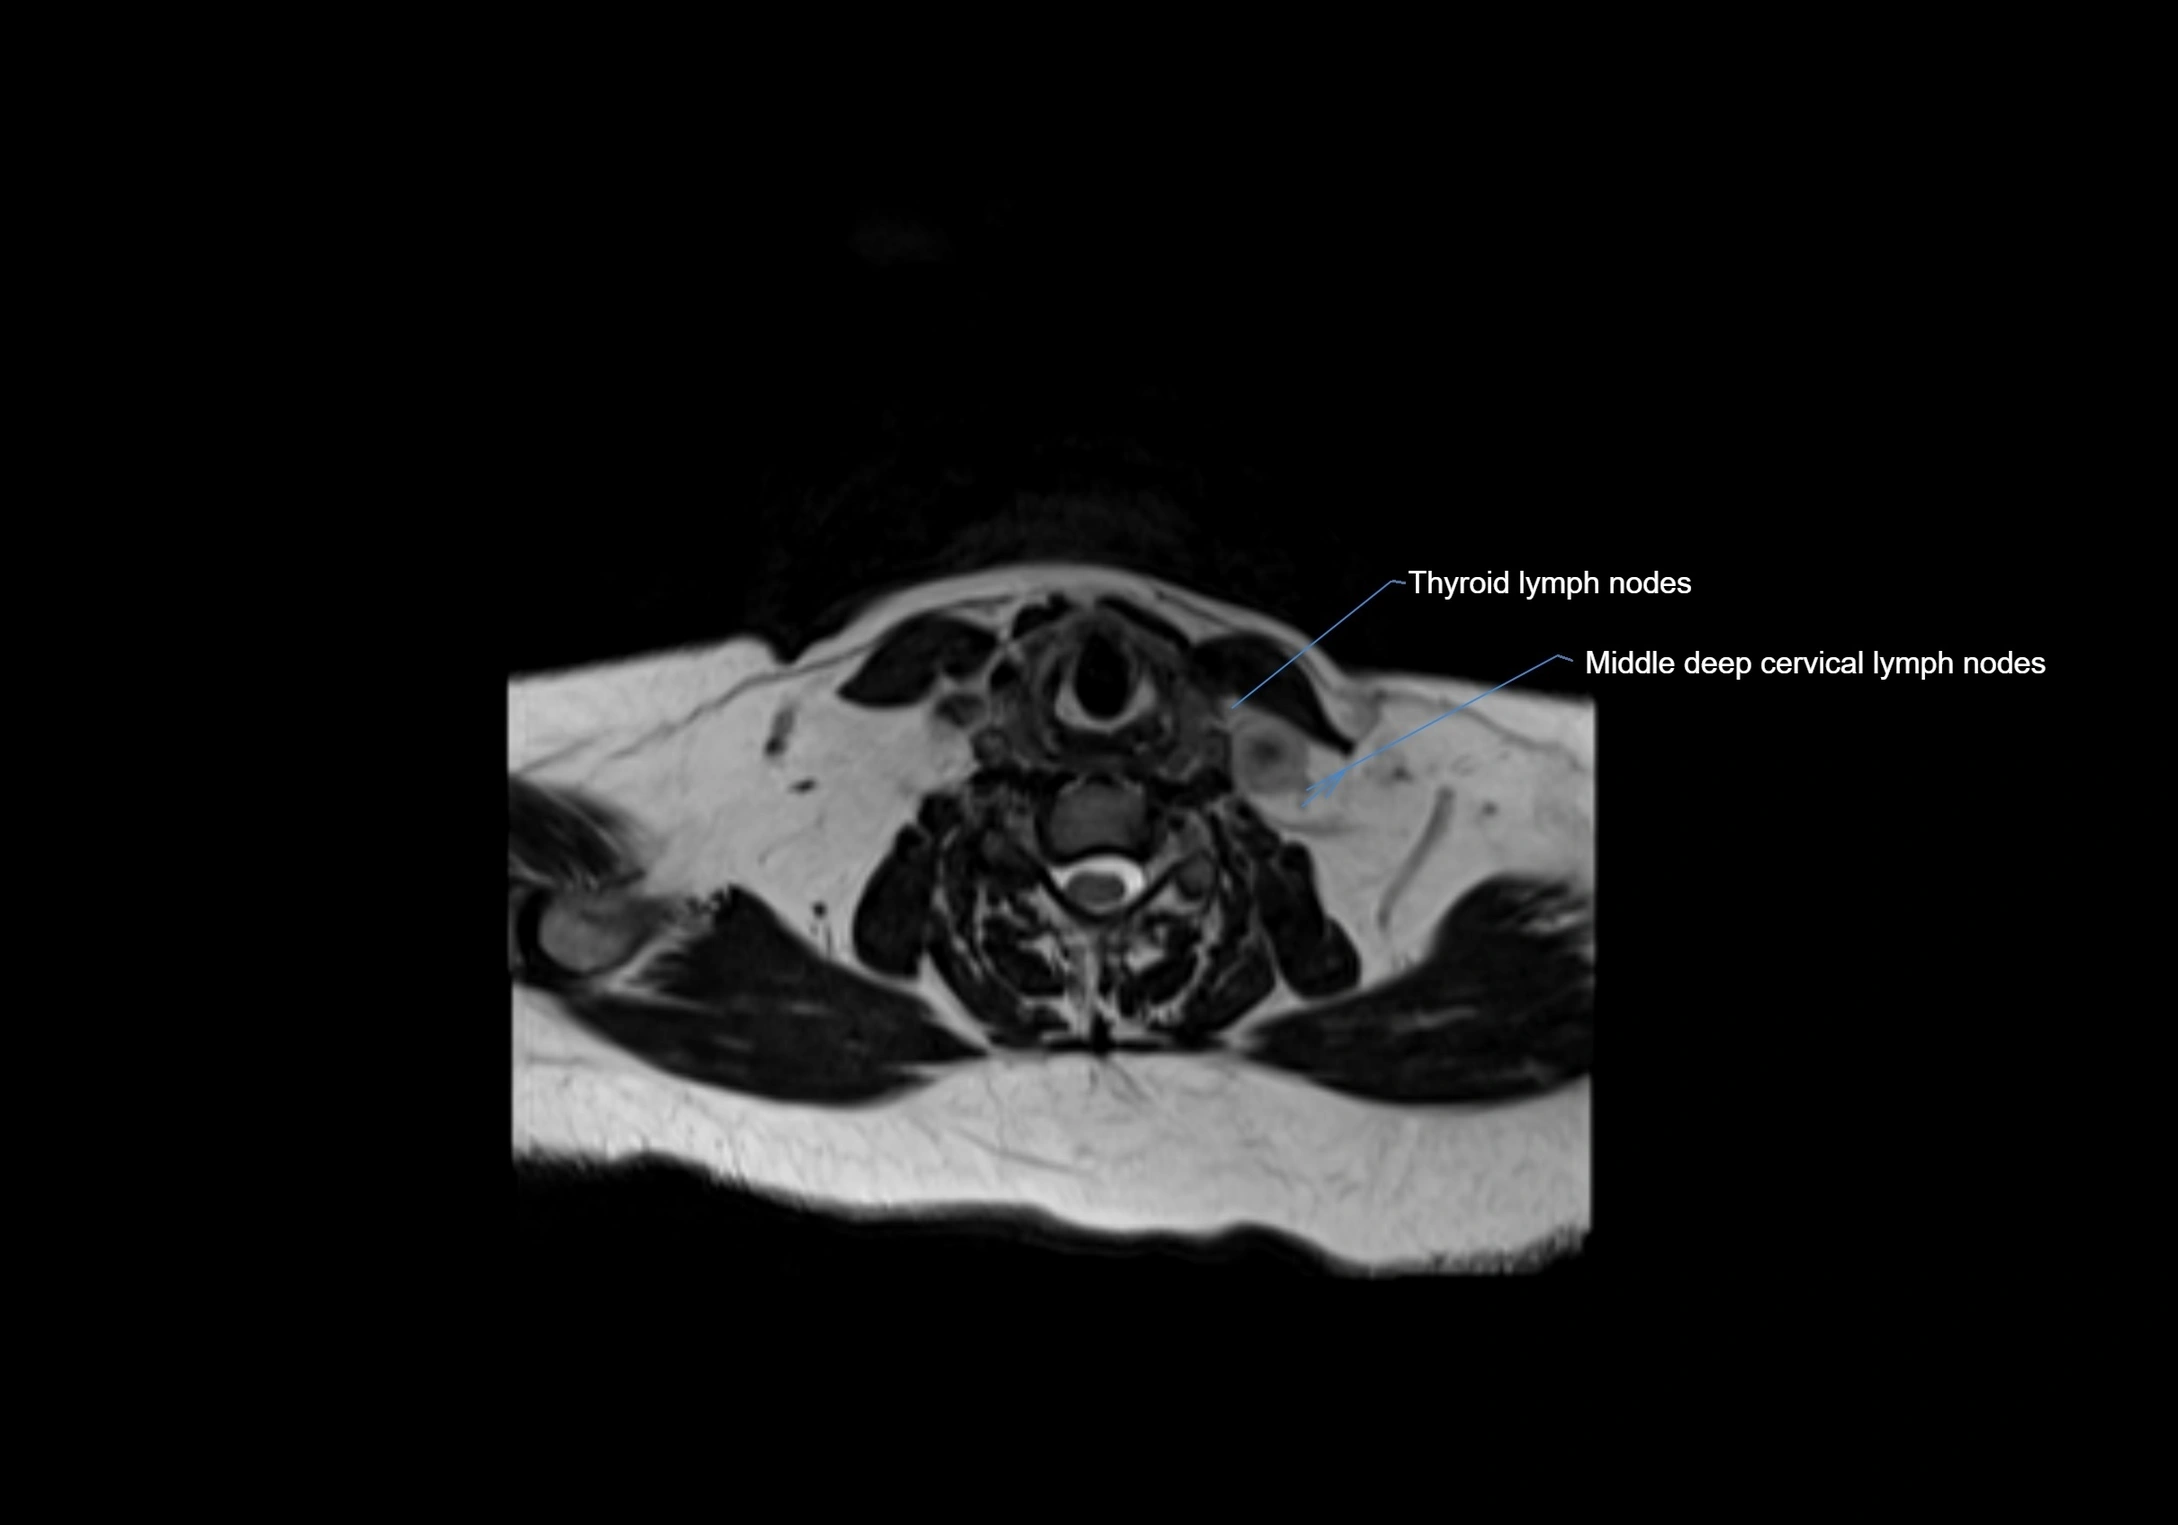

Accessory lymph nodes are small, secondary lymph nodes located along the main facial and cervical lymphatic chains, often adjacent to primary lymph nodes, such as preauricular, submandibular, or occipital nodes. They are typically less than 5 mm in diameter, embedded within subcutaneous fat or connective tissue, and may be variable in number and location. These nodes provide additional filtration and immune surveillance for lymph collected from the face, scalp, and neck regions. Accessory lymph nodes are usually non-palpable in healthy individuals but may enlarge in response to infection, inflammation, or metastasis, making them clinically significant.

• Found along primary lymph node chains, including preauricular, submandibular, parotid, and occipital regions

MRI Appearance

T1-weighted images:

• Normal accessory nodes appear as small, oval hypointense to intermediate signal structures within subcutaneous fat

• Surrounded by hyperintense fat, enhancing contrast for visualization

• Pathological nodes may appear enlarged or rounded, sometimes with cortical thickening

T2-weighted images:

• Nodes show intermediate signal, with surrounding fat bright

• Useful for detecting edema, inflammation, or infiltration

• Fatty hilum may appear slightly hyperintense relative to cortex